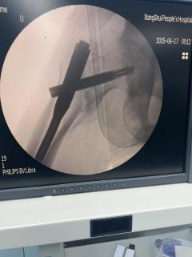

微创技术应用:采用闭合复位髓内钉固定术,减少软组织损伤,手术时间控制在1小时内。

医院数据显示,近五年来80岁以上髋部骨折患者实施手术221余例,90-99岁髋部骨折患者实施手术71例。100岁以上髋部骨折患者实施手术4例。